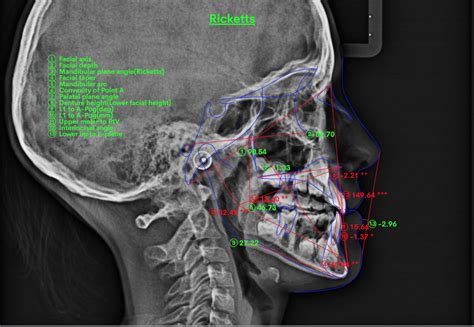

- El estudio de Ricketts.

Mediciones Angulares

Mediciones angulares:

- S.N.A

- S.N.B

- A.N.B

- N.S.Gn (eje de Crecimiento)

- N.S.Ba (ángulo de la base craneal)

- Ar. Go. Gn (ángulo goniaco)

- 1 - SpP / (ángulo del incisivo superior)

- 1 - M.I. (ángulo incisivo inferior)

- SpP - MI (ángulo de las bases)

- SpP - SN (ángulo del plano palatal)

- Ocl - SN (ángulo del plano oclusal)